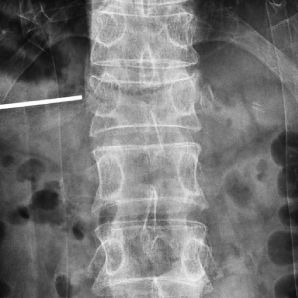

Le Compax 500 (Pro) est livré avec la dernière technologie numérique de toute la chaîne d'imagerie, améliorant de manière approfondie la qualité des images peropératoires en orthopédie et fournissant des détails d'image plus riches pour le diagnostic clinique. Le produit est équipé d'un détecteur de panel plat dynamique de grande taille, avec des images claires et délicates qui répondent à une variété d'examens cliniques. La grande géométrie du bras C et divers conceptions humanisées peuvent facilement répondre aux besoins chirurgicaux des patients de toutes tailles, fournissant des solutions d'imagerie plus précises, plus intelligentes et plus efficaces pour le diagnostic et le traitement des maladies cliniques telles que l'orthopédie, la chirurgie vertébrale et les procédures de gestion de la douleur.

Qualité d'image supérieure avec FPD

Équipé de son détecteur à panneaux plat de 21 * 21 cm ou 30 * 30 cm, ce système produit des images claires et délicates tout en maintenant une large gamme dynamique, offrant une grande visualisation des détails avec un grand champ de vision.